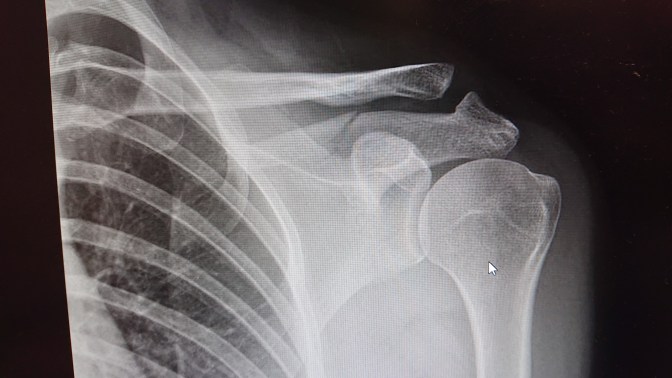

I’d broken my acromion at the top of my shoulder blade.